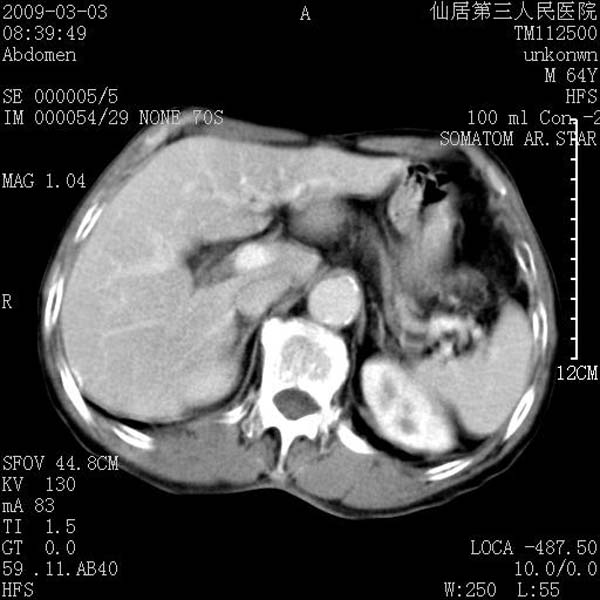

标题: CT18469:男性,64y,体检B超示肝脏低回声肿块,有胃溃疡手术 [打印本页]

标题: CT18469:男性,64y,体检B超示肝脏低回声肿块,有胃溃疡手术

患者,男性,64y,体检b超示肝脏低回声肿块,有胃溃疡手术史。

考虑----胃肠道间质瘤可能性大

从平扫及增强的特点来看,支持肝脏腺瘤并出血。

考虑胃间质瘤可能性大。

胃肠道间质瘤!

ct值呢?感觉没强化,象囊性。

考虑肝静脉韧带裂区良性占位性病变(囊肿?)。

考虑肝囊肿并出血可能性大.

考虑高密度囊肿可能性大